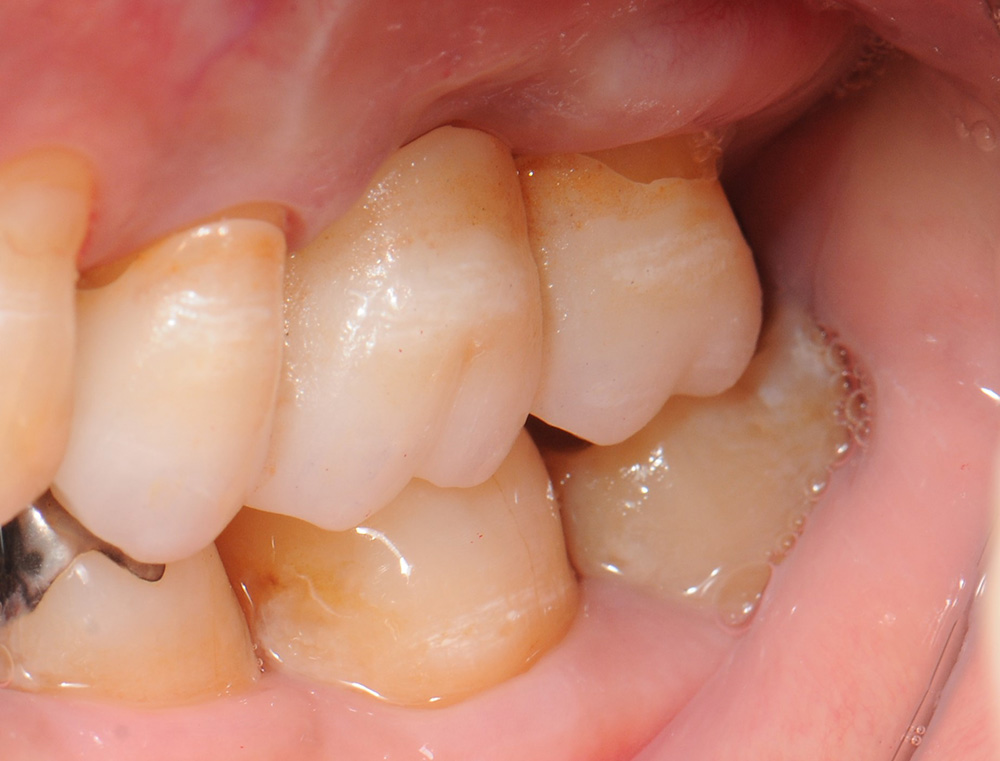

case9 症例(セラミックブリッジ)

治療前

治療後

| 費用(税込み) | 198,000円 |

|---|---|

| メリット・デメリット | 歯を削る、一時的に知覚過敏になる |

| 治療回数 | 5-6回(歯肉・仮歯の調整含む) |

| 主訴 | 奥歯が無い |